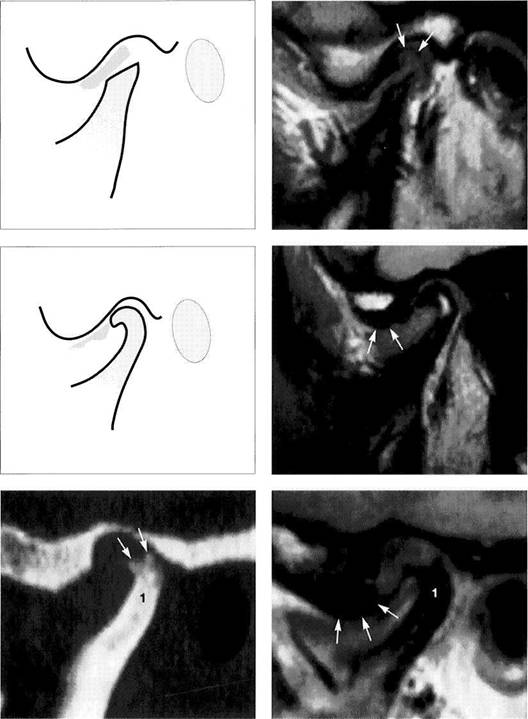

Physiological disk position

Under normal conditions, the pars intermedia (*) of the disk lies be­tween the anterosuperior curva­ture of the condyle and the articular protuberance (arrows). The posi­tion of the posterior border of the pars posterior relative to the vertex of the condyle varies according to the inclination of the protuberance and is therefore not a reliable pa­rameter.

The arrows in this schematic draw­ing mark the relative positions of the condyle and the pars interme­dia to one another.

Insidious disk displacement or a tendency to anterior disk displacement

The pars intermedia lies well in front of the shortest distance be­tween condyle and protuberance (arrows), but the pars posterior (1) still lies on the condyle. Clinically, there are no clicking sounds during jaw opening.

Right: Drawing of a joint with a ten­dency to anterior disk displace­ment. The arrows mark the discrep­ancy between pars intermedia and condyle.

Definite disk displacement

Left: Both the pars intermedia (*) and the posterior border of the pars posterior lie in front of the most anterosuperior curvature of the condyle (arrows). Unless this is a case of disk displacement without repositioning, a clicking sound will occur regularly during jaw opening.

Right: Schematic drawing of a defi­nite anterior disk displacement. The arrows mark the discrepancy between the pars intermedia and condyle.